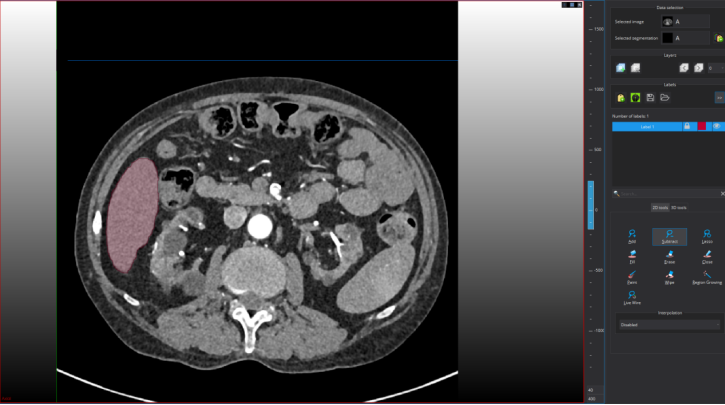

修改后的标注如下图所示:

尽管上图标注看似不错,但仍可以进一步精细修改。鼠标指向标注目标区域,按住鼠标右键进行放大

精修后的可视化如图: